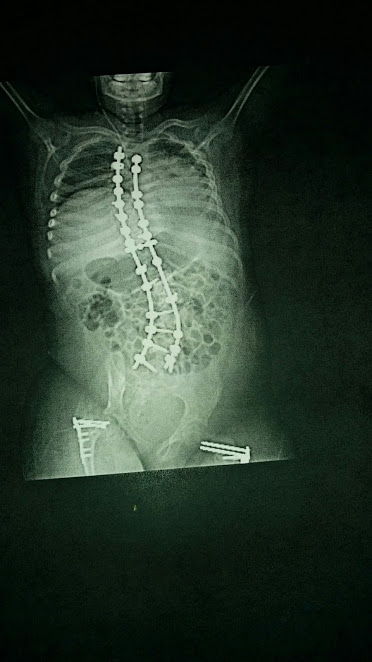

Nu kommer jag troligen skriva de tre sista ”inläggen” om Albert tre dagar i följd , de är otroligt jobbiga att skriva och säkert också att läsa för vissa. Redan när Albert var 7-8 år fick vi veta att han led av skolios eller att hans funktionshinder gjorde att ryggen blev sned då hans muskler drog åt olika håll.

Vi fick informationen att i framtiden måste vi nog operera men för att skjuta på det så länge som möjligt så skulle han ha väst så mycket det gick för att hjälpa kroppen att hålla ryggen rak. Jag vet inte hur många gånger vi (ofta Milla och assistenter) varit och provat ut, justerat och bytt väst, ortoser och ståskal Det blev ju en ständig process och det kändes allt för ofta som att när vi fick en ny väst, ståskal eller ortoser så hade han nästan växt ur dem.

Hösten 2014 tog vi beslutet att steloperera ryggen på honom, det kan låta som elakt och vi funderade också hur det skulle bli ? Jag och Milla frågade många gånger hur det skulle bli rent praktiskt då albert älskade att ligga på mage. Kommer han kunna lyfta nacken ? Hur stel blir han, hur gör vi för att förflytta ? Kommer det göra ont länge? Det gör så ont att inte min älskade ängel inte fick uppleva hur bra det blev när allt var klart.

Läkningen gick fortare än vi förväntat oss han var uppe och satt i rullstlolen redan efter nån dag. Allt gick nog så bra vi kunde önska oss och jag började tro på en framtid igen.

Efter tio dagar blev det dags för hemfärd, när vi satt på röntgen och gjorde den sista kollen var jag så glad så jag köpte en bil.